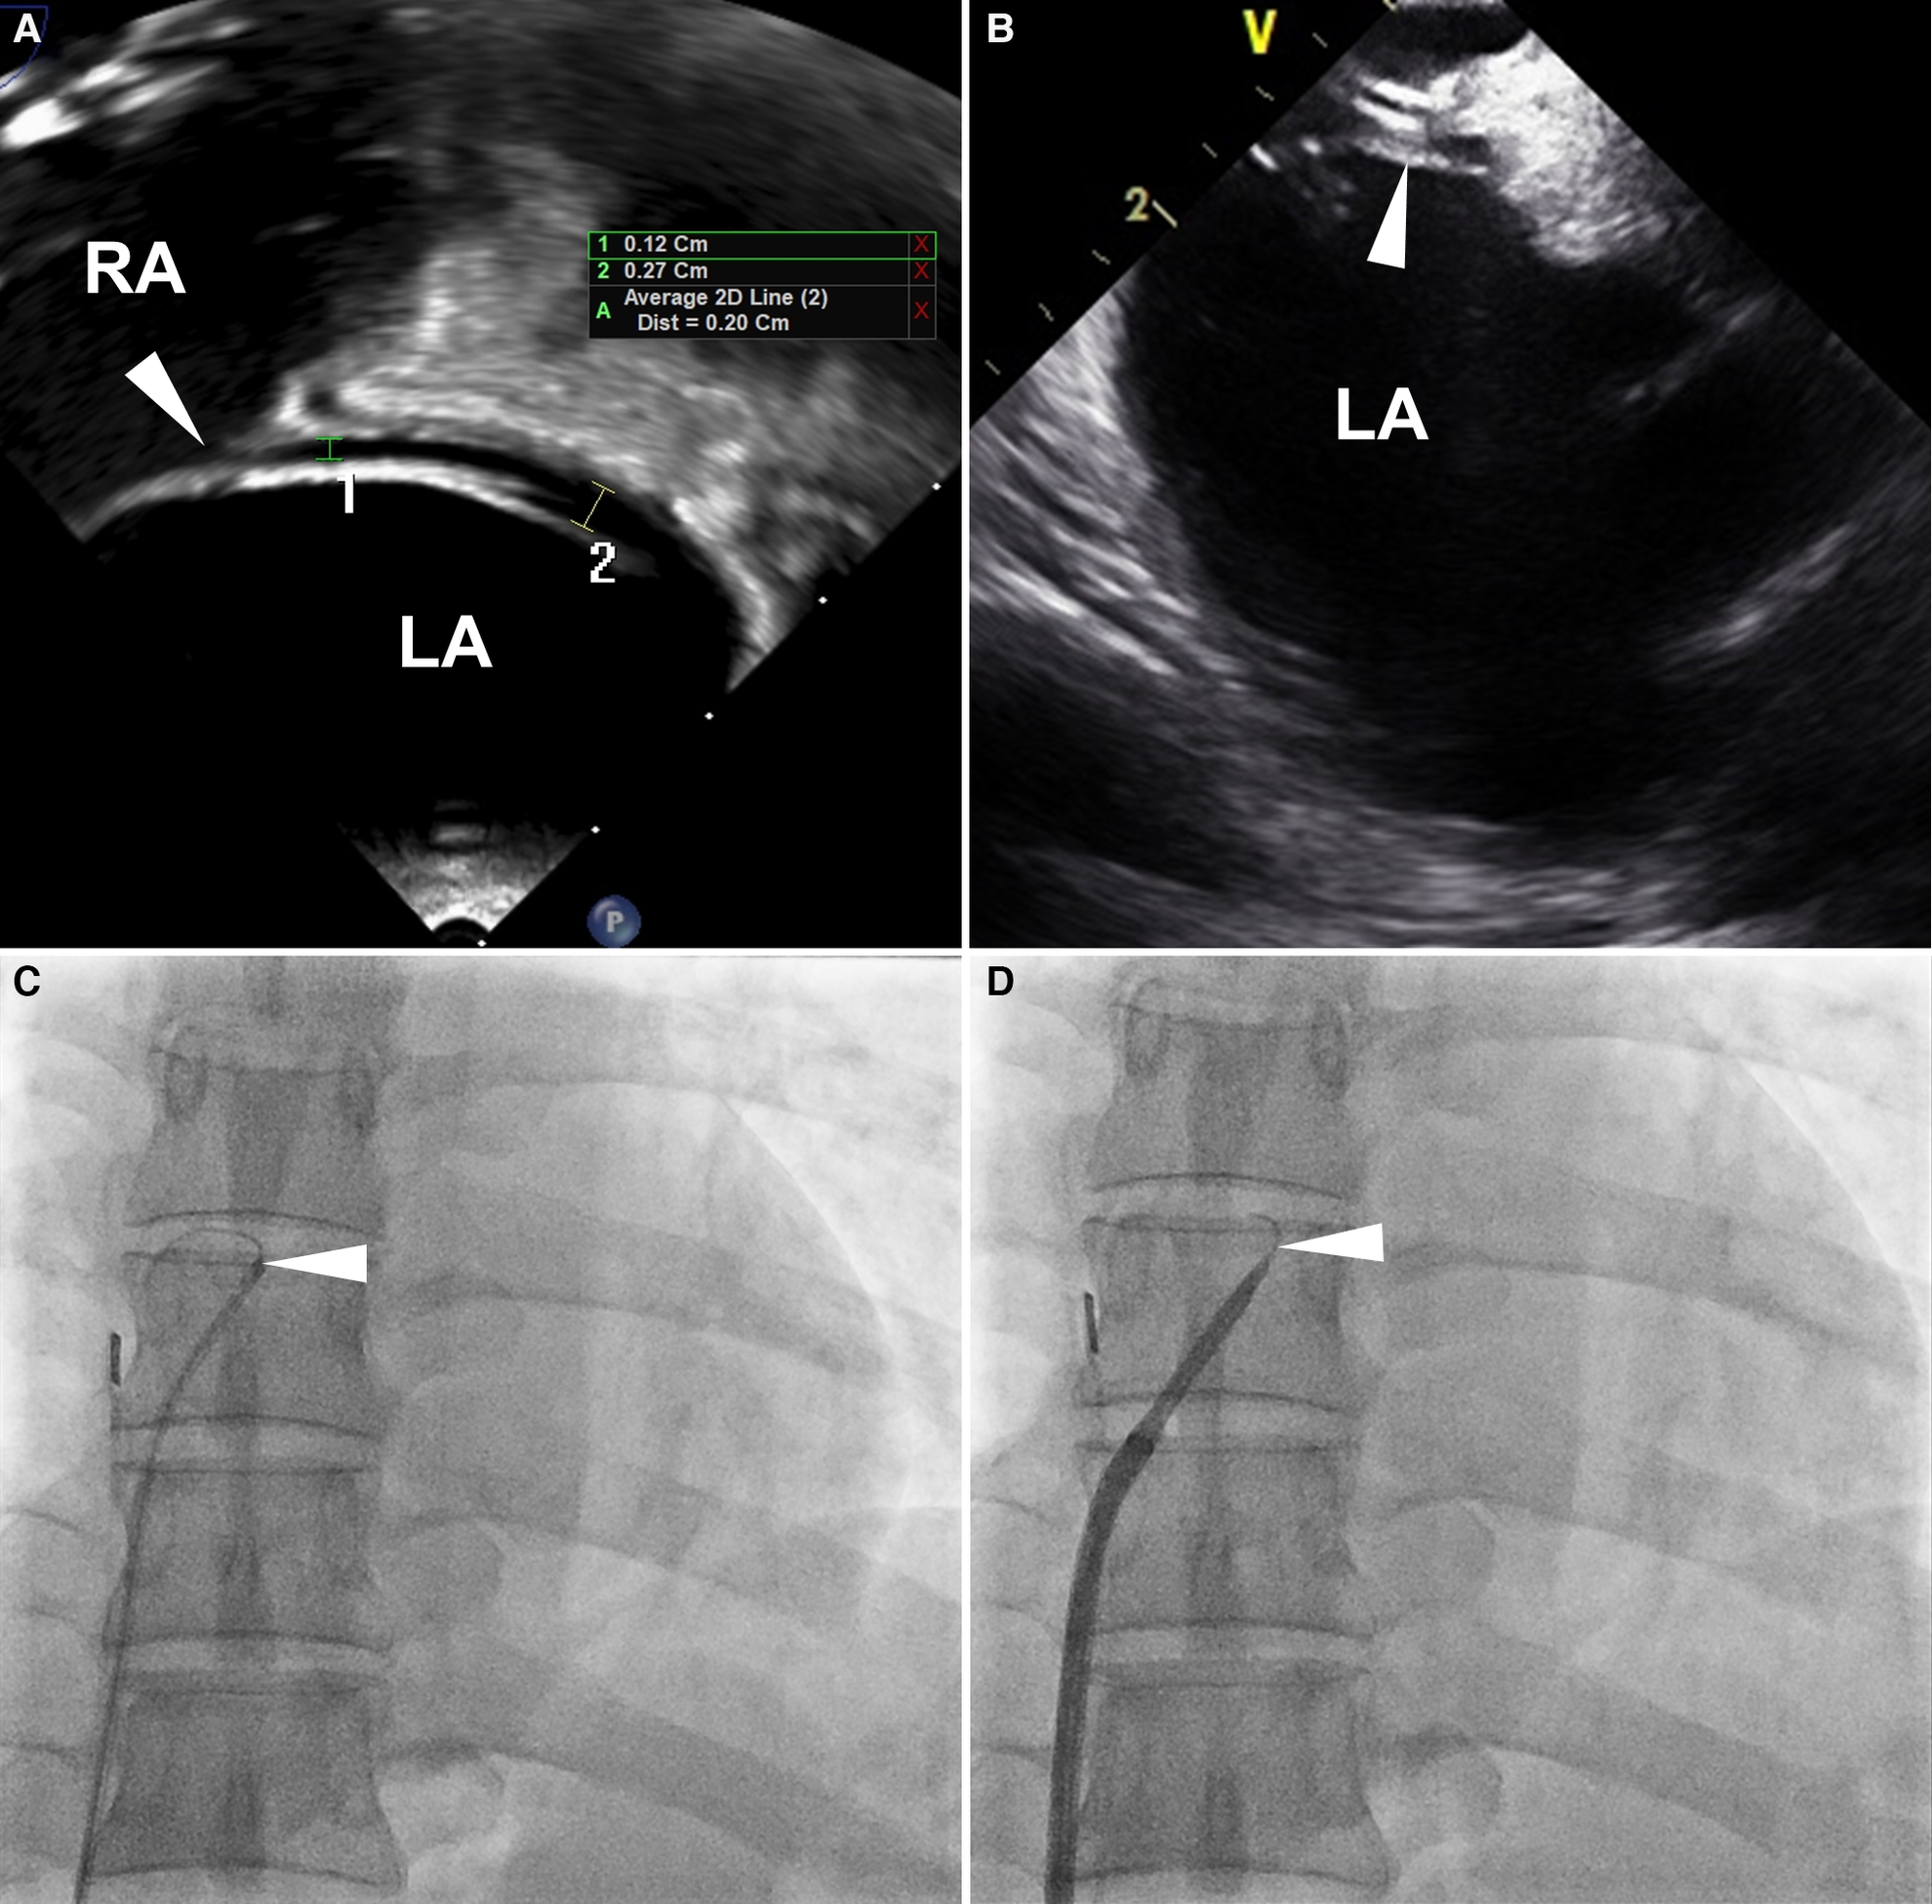

For PFO closure, a soft-tipped 0.035-inch guidewire or a multipurpose (MP) catheter is introduced through the PFO tunnel from the right atrium (RA) to the left atrium (LA) (10–13). However, in some cases, the guidewire or catheter fails to traverse the PFO tunnel, even in patients with high-grade shunts (Figure 1). In these patients, transseptal puncture around the PFO tunnel can be performed to facilitate wire or catheter passage (14–17). Nonetheless, our previous data indicate a higher incidence of recurrent stroke or TIA and residual shunt with this technique compared to the standard PFO closure technique (18). Consequently, transseptal puncture is an invasive procedure with a potential for poor outcomes, and its use in the treatment of uncrossable PFOs may be carefully considered.

Figure 1

Definition of uncrossable PFO. Images from a 53-year-old man with an uncrossable PFO. (A) TEE 90-degree bicaval view shows a long-tunnel PFO. The probe was additionally rotated to optimize the visibility of the PFO tunnel in the bicaval view. (B) ICE imaging for PFO closure guidance. (C) 6 Fr MP catheter and 0.035-inch guidewire failed to pass through PFO. (D) SL1TM sheath replacement didn't resolve the issue. White arrowheads indicate PFO. ICE, intracardiac echocardiography; LA, left atrium; MP, multipurpose; PFO, patent foramen ovale; RA, right atrium; TEE, transesophageal echocardiography.